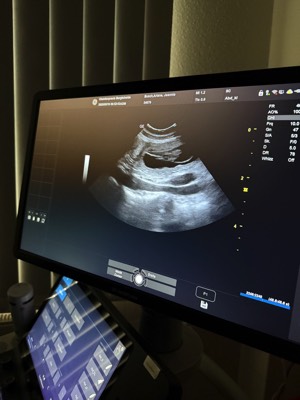

Unsere bezaubernde Jeannie „Tova‘s Riesling Surprise in Germany“ wurde Ende April von unserem charmanten Mio „Golden Nugget's Achilles“ gedeckt.